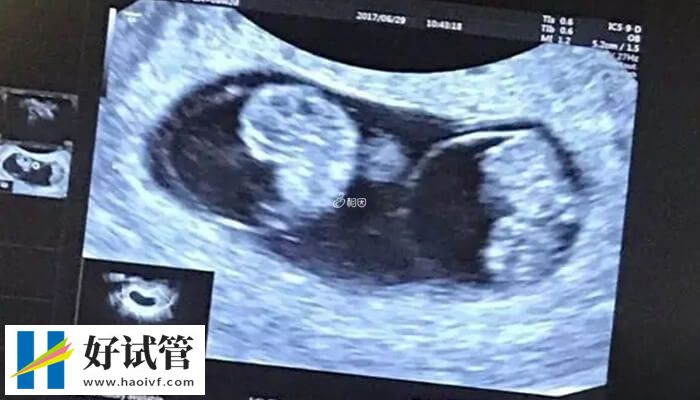

1、b超检查

女性怀孕初期怀的是双胞胎,要通过b超检查确诊,不能仅凭自己的感觉。通常怀孕40天左右,b超检查可显示宫腔内有孕囊。这时候如果发现两个孕囊,就可以确认怀的是双胞胎;

- 孕早期通过超声检查可以明确判断双胎妊娠,如果是异卵双胞胎,孕6周左右可以发现两个孕囊。如果是同卵双胞胎,在孕13周左右可以发现,可以显示两次心跳;